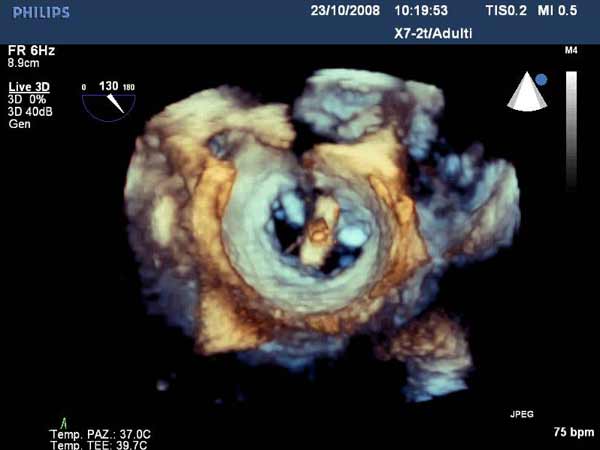

In absence of controlled clinical trial data which are forthcoming from the EVEREST II randomized study, the indications for the MitraClip therapy are currently based on registry experience and will evolve as the technique improves, experience is growing and the data to demonstrate efficacy and safety becomes available. At this time, the best indication for the MitraClip therapy is for symptomatic patients with clinically significant functional or degenerative MR who are at high or increased risk for open heart surgery. From a pure technical standpoint, the procedure so far has only been demonstrated in a subgroup of patients with specific anatomical characteristics which are summarized below and shown in Figure 3. Anatomic suitability is assessed by transesophageal echocardiography, and mitral regurgitation should originate from the central portion of the valve involving the A2-P2 segments, since the device is not ideal to work in the commissures at this time; the mechanism of MR can be either a prolapse/flail or MR due to restricted leaflet motion unrelated to rheumatic disease; the separation between the two leaflets at the site of regurgitation should be limited; severe annular dilatation and/or severe calcification should be absent or is relevant. In case of flail, the flail segment width should be less than 15 mm, and the flail gap less than 10 mm. Figure 4 is a 3D echo image of a patient with posterior leaflet prolapse selected for MitraClip therapy. In case of functional MR, the leaflets should have a minimal residual tissue available for coaptation with the MitraClip device. Figure 5 shows 2D color Doppler jet extension over the coaptation line at TEE short axis transgastric view, while Figure 6 shows the tenting area and the coaptation depth of a patient undergoing MitraClip implant.